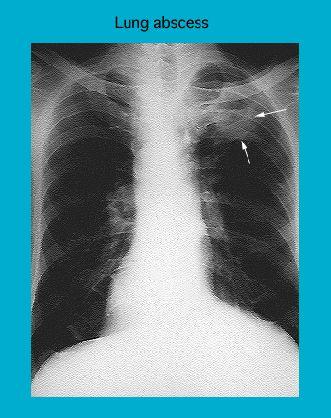

Radiograph of lung abscess